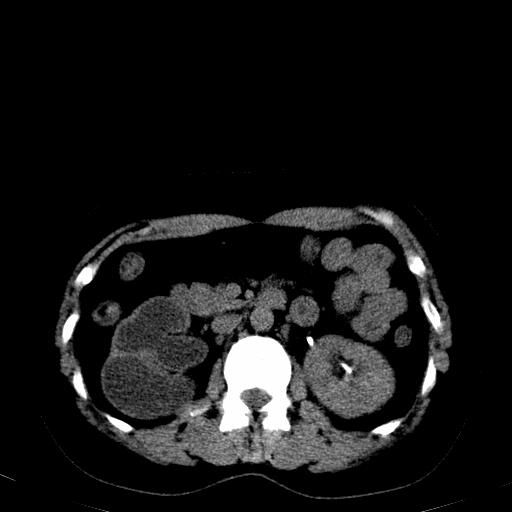

右肾多发囊肿,左肾、左输尿管结石

右侧肾积水、左侧肾结石

右侧肾积水、左侧肾结石  ,要排除右肾结核可能。

1)不排除右肾结核可能。2)左肾及左输尿管上段结石?

左肾不是结石,是造影后改变.右肾积水,功能仅存.